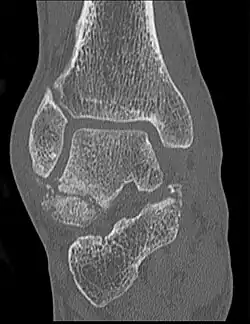

Die Verletzung stellt sich mit Schmerzen und Schwellung in der Fußwurzel und außen am Fuß dar. Diese Befunde können leicht mit einer Verstauchung, Zerrung oder einem Bänderriss am Außenknöchel verwechselt werden. Dieses insbesondere, wenn nicht bekannt ist, dass es sich um einen Snowboarder handelt. Auch ist der Knochenbruch auf Übersichtsröntgenbildern manchmal schwer zu erkennen. Eine Computertomographie kann die Bruchlinien überlagerungsfrei darstellen und ist für die Planung der richtigen Therapie hilfreich.[6][14][7][12]

Je nachdem, wie die einzelnen Bruchlinien verlaufen und wie groß die Fragmente sind, ist eine unterschiedliche Behandlung anzustreben. Eine Klassifikation in drei verschiedene Frakturtypen wurde schon 1965 vorgeschlagen.[2] Die heute gebräuchliche Einteilung stammt von McCrory und Bladin (1996):[5]

- Typ I: Kleines Fragment an der Spitze des Processus lateralis ohne Gelenkbeteiligung.

- Typ II: Ein größeres Fragment mit Beteiligung der Gelenkflächen zum Außenknöchel und nach caudal zum Calcaneus. Dieser Typ kann operativ verschraubt werden.

- Typ III: Trümmerbruch mit vielen Kleinfragmenten.